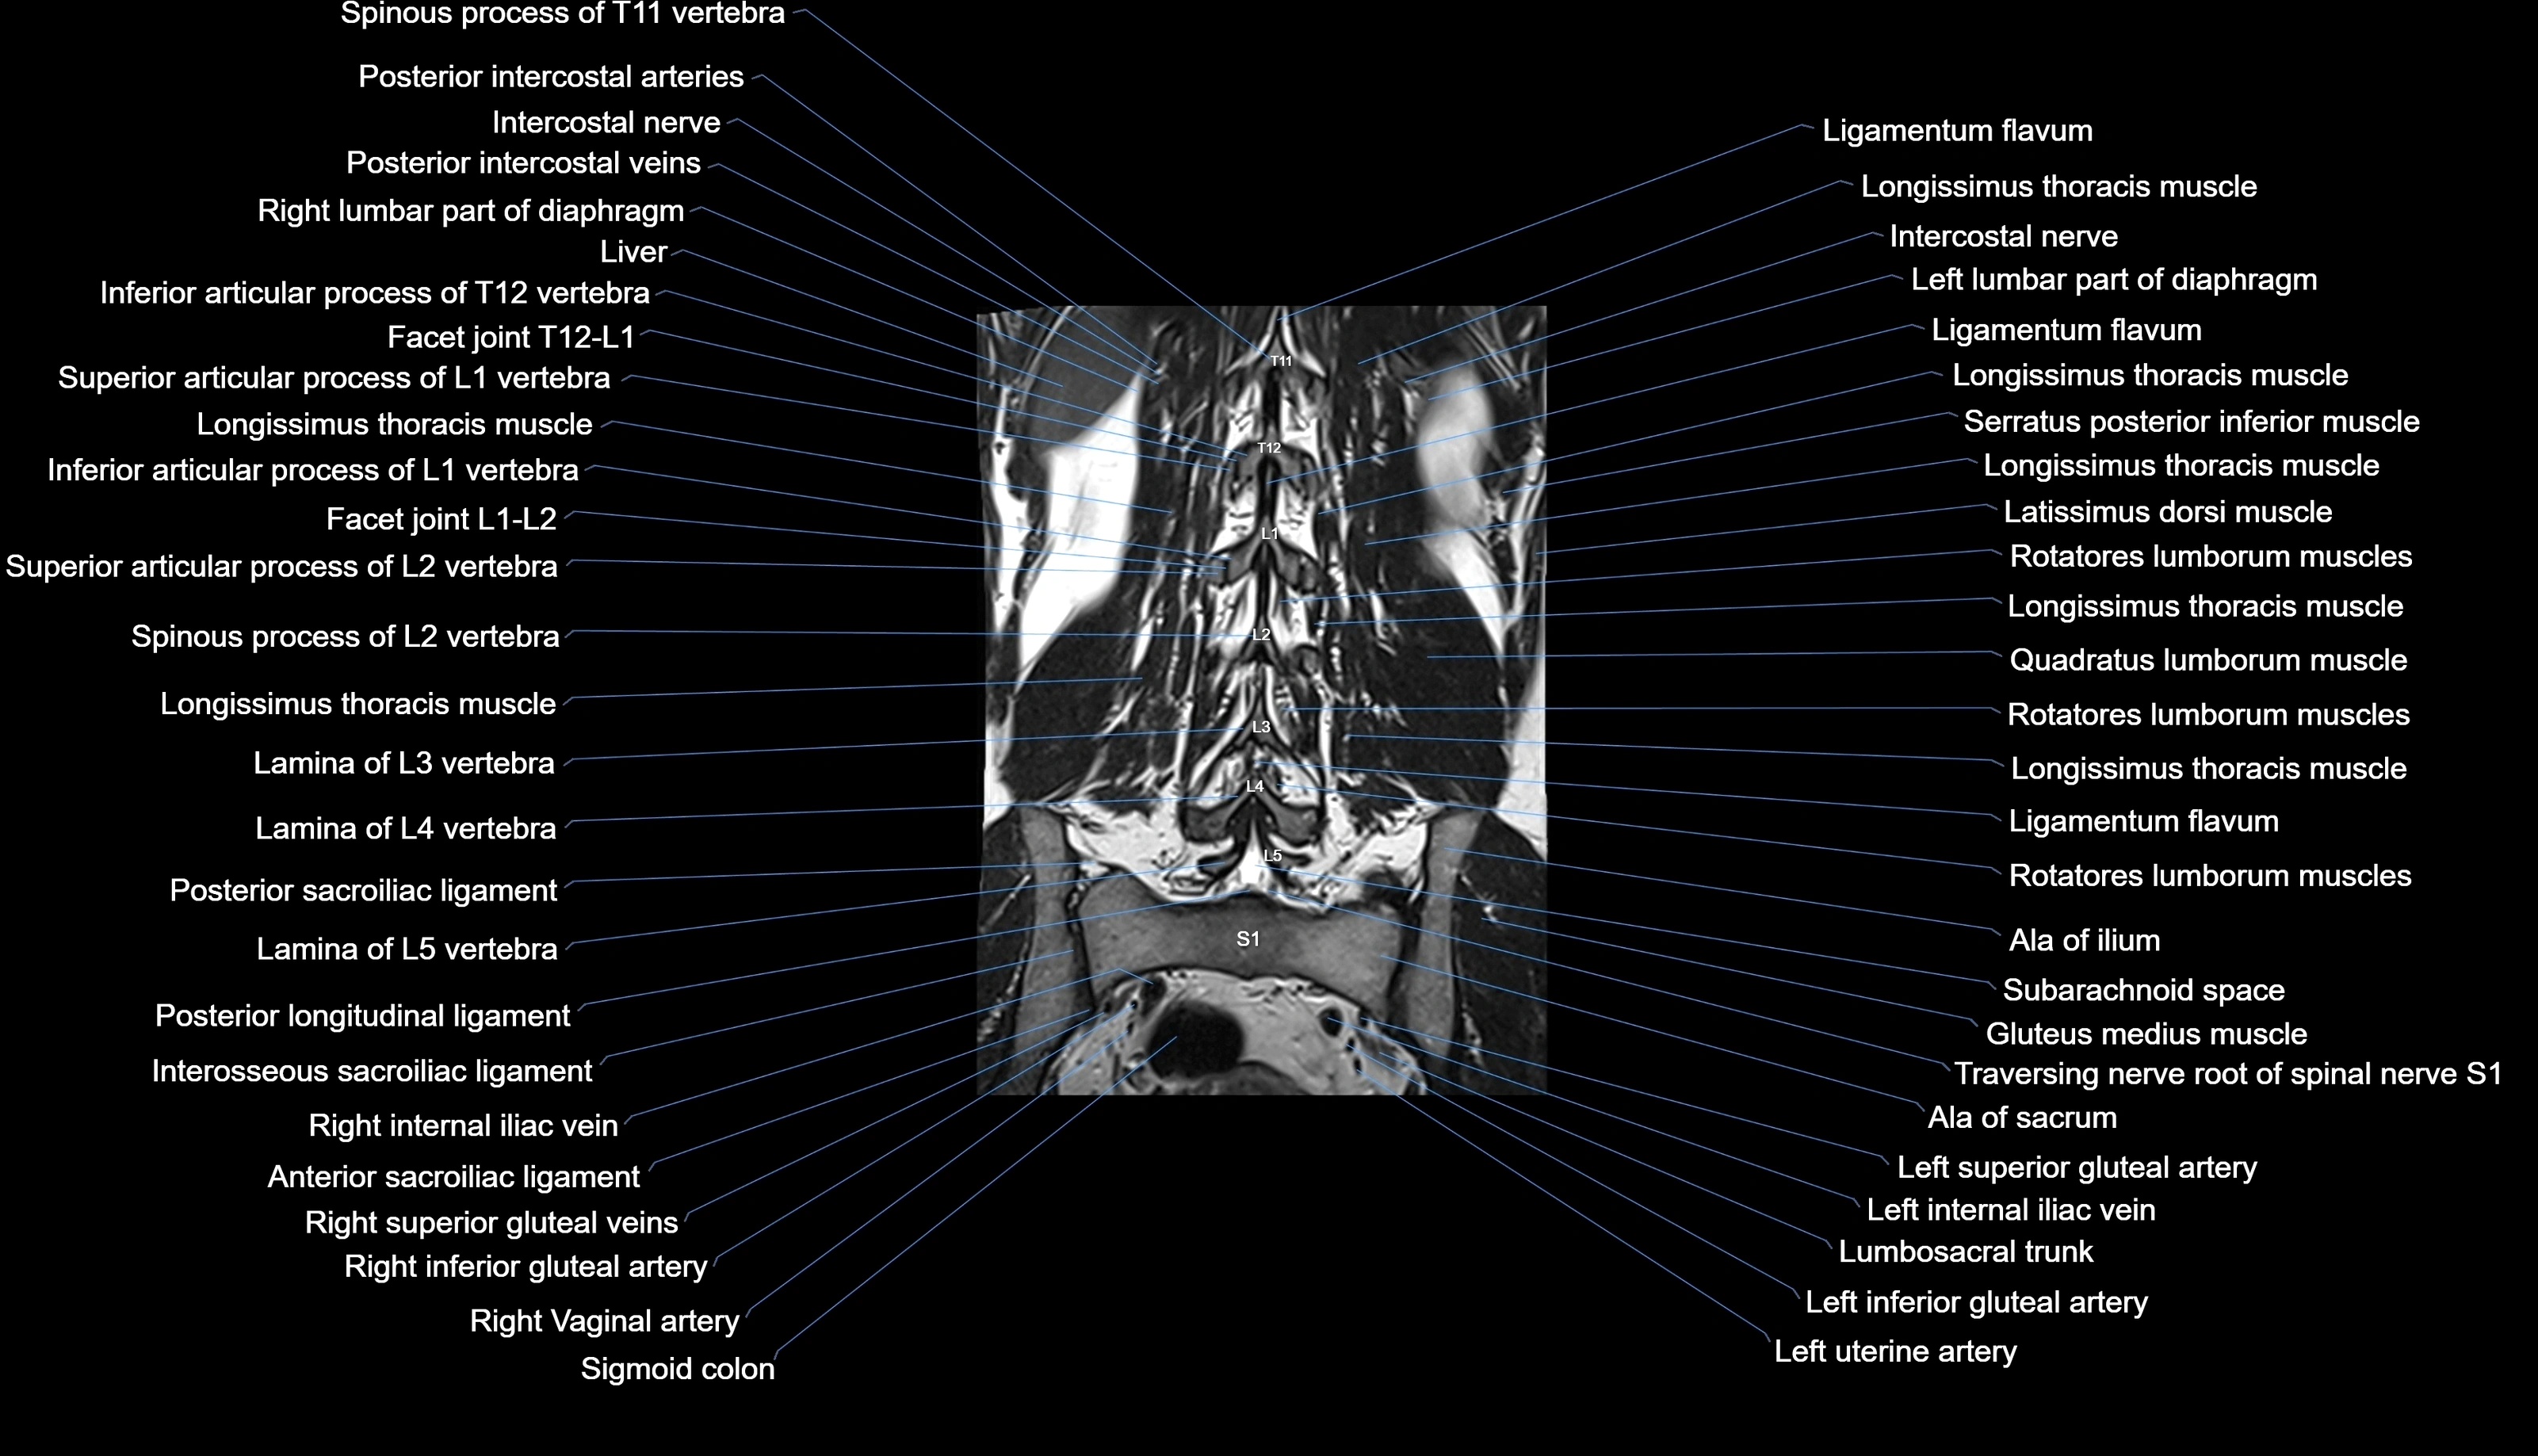

MRI images